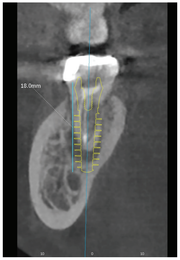

23세 남성 환자가 37번의 극심한 통증으로 내원했다. 해당 치아의 발치가 필요했으나 mandibular canal까지 거리가 3mm 정도로 가까워 safety margin을 확보하기가 어려운 상황이었다. [그림 1]

또한 치은연으로부터 18mm 깊이를 들어가야 잔존골 1~2mm에서 고정을 얻을 수 있다고 판단됐다.

37번 치아의 치근 형태는 근원심 치근이 붙어 있는 one root 형상이었으며 근심쪽으로 잔존골이 매우 부족한 상황이었다. 이처럼 불리한 조건에도 불구하고 발치 후 즉시 식립을 계획한다면 37번의 근심과 mandibular canal 상방 및 lingual cortical plate에서 고정을 기대할 수 있었다. [그림 2]